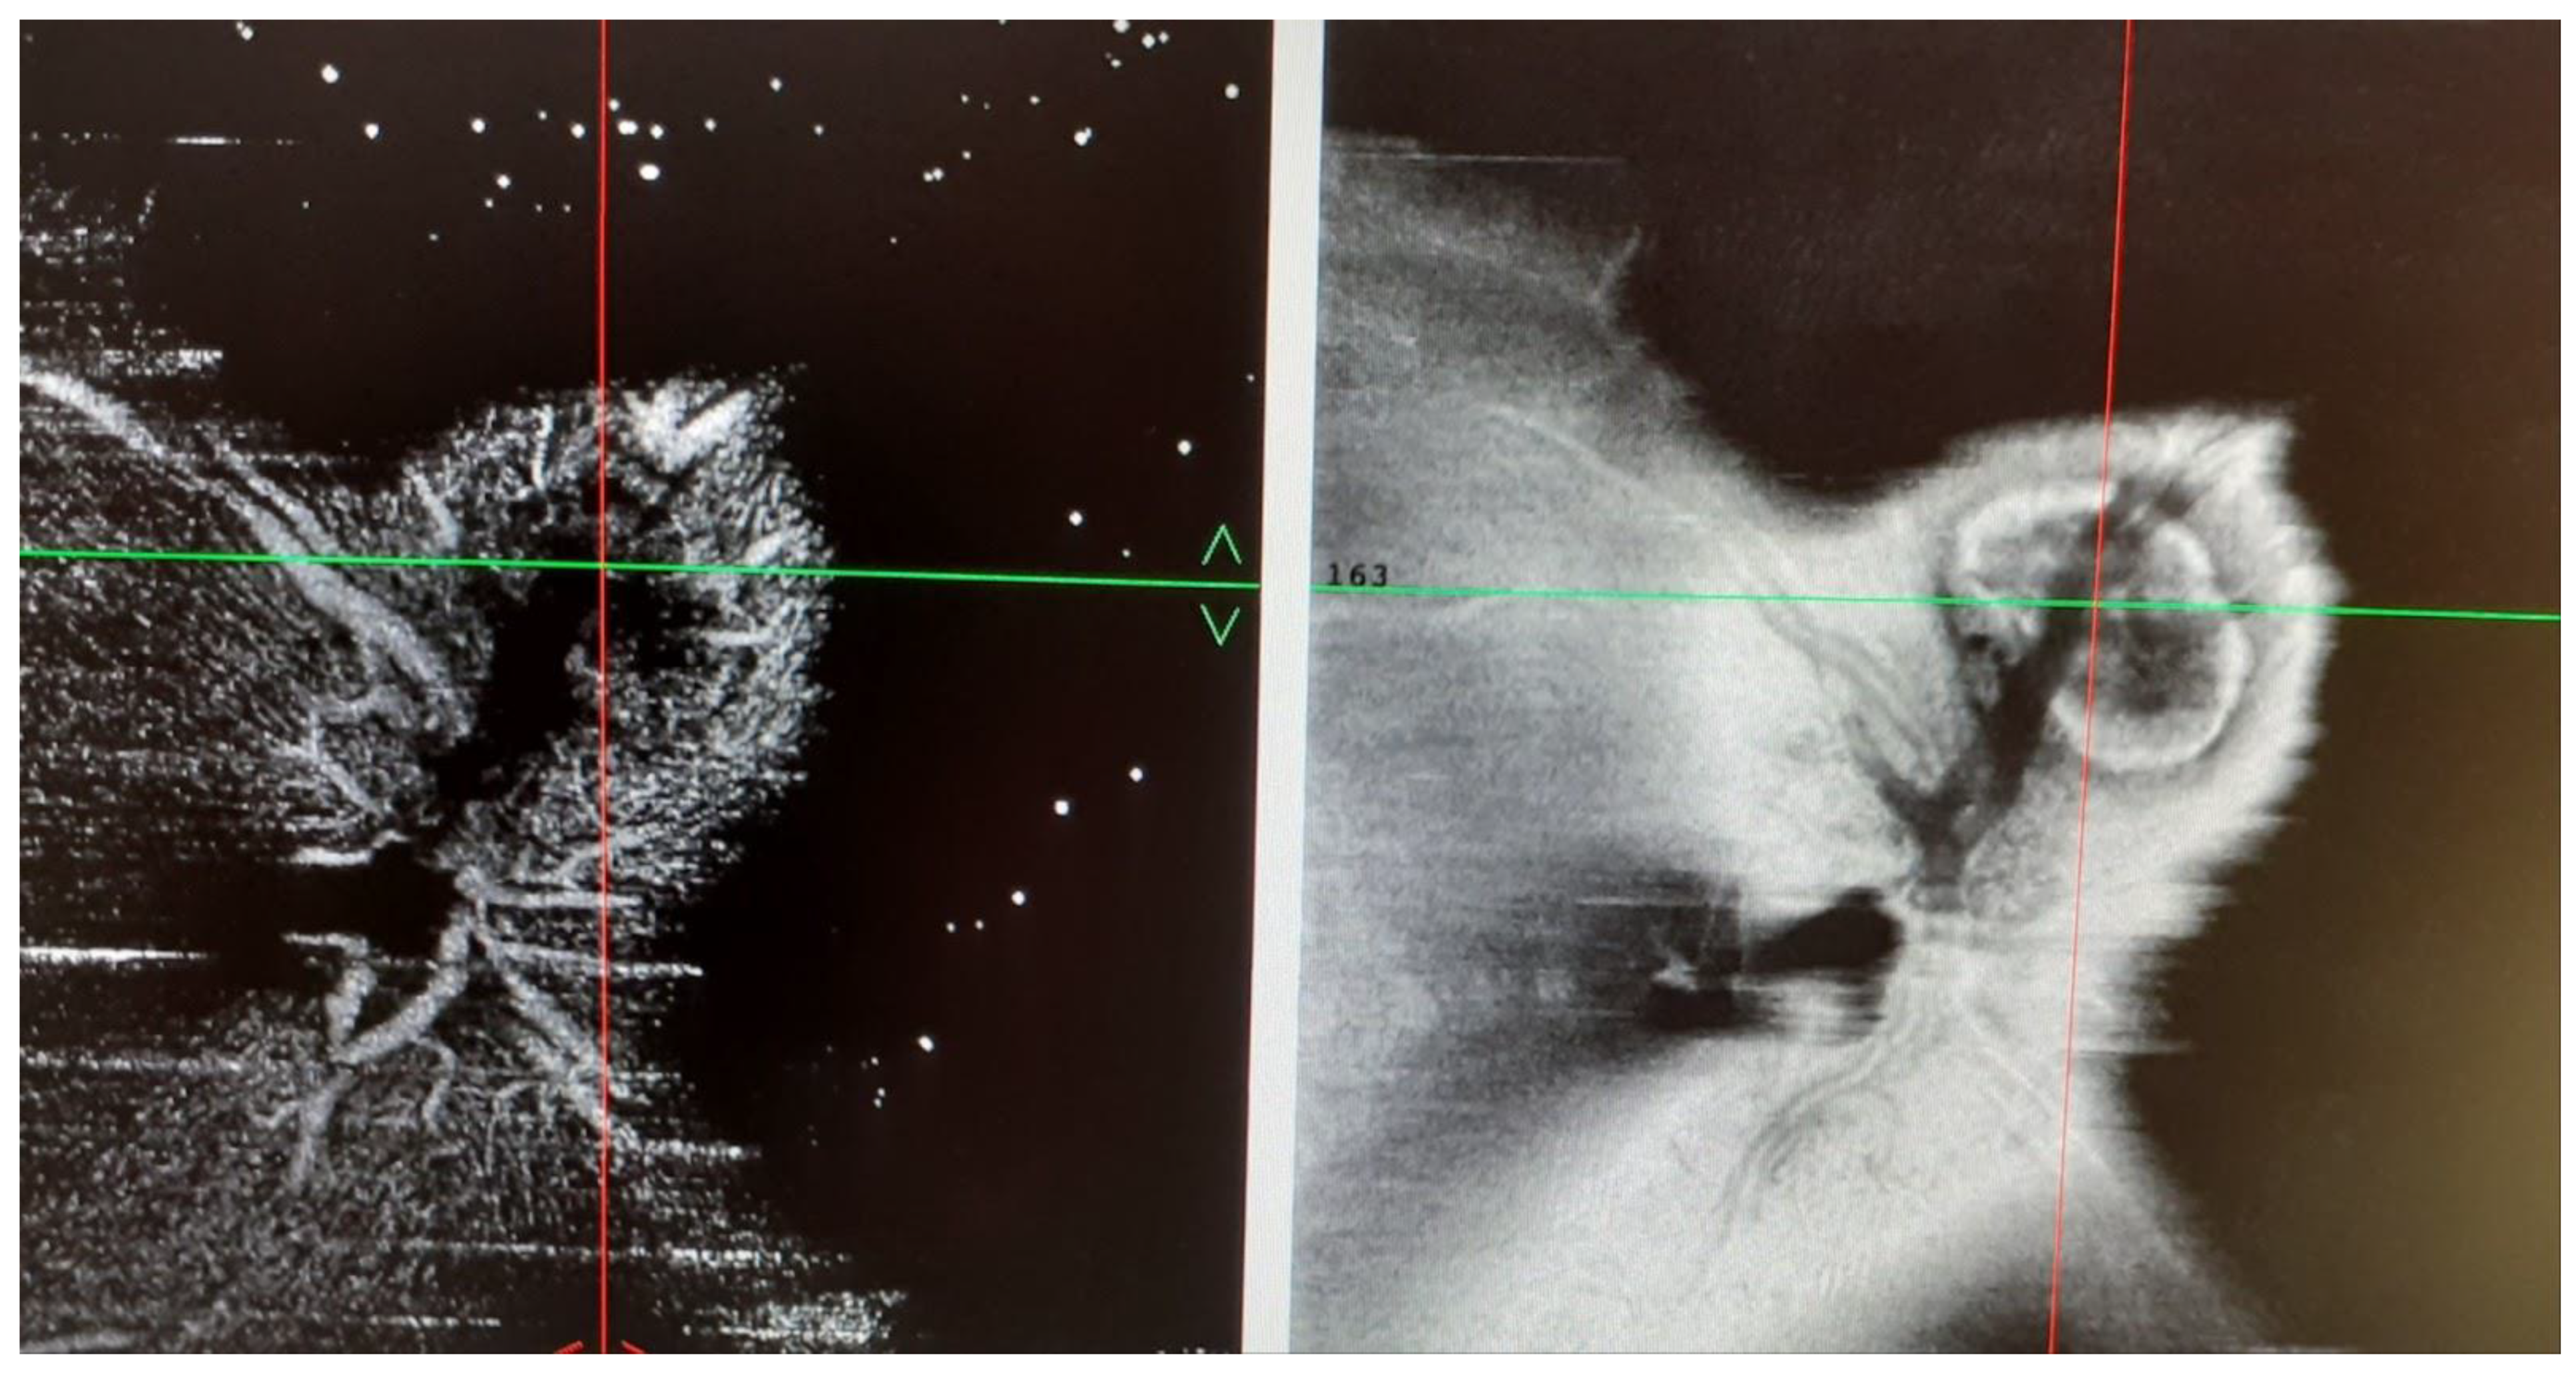

Juxtapapillary Choroidal Neovascularization in a Young Woman with Tubulointerstitial Nephritis and Uveitis (TINU) Syndrome with Onset in Pediatric Age

2. Case Presentation